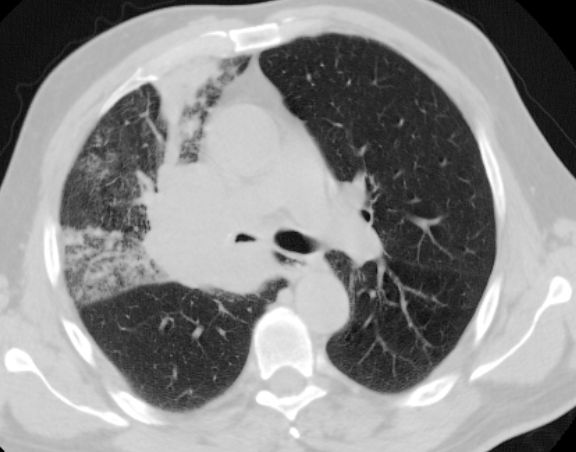

Kleinzelliges Karzinom des rechten Oberlappens. T3 N2 Mo. Lungenfenster ![]() |